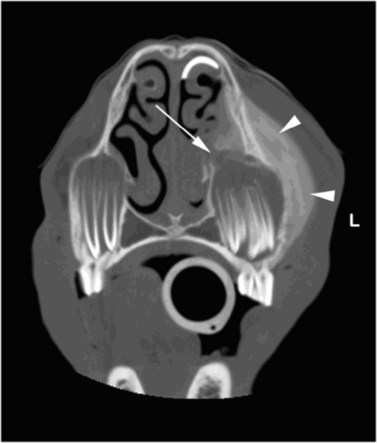

image image image

Fig. 13.36 Polydontia. Supernumerary maxillary cheek teeth (Triadan12s) are the most common supernumerary cheek teeth in horses. The 12 is usually markedly overgrown as in (A) but may be unerupted as in (B) if there is inadequate space (overcrowding). Note the abnormal shape of the apical area of the 112. (C) An example of overgrown bilateral supernumerary mandibular 12s.